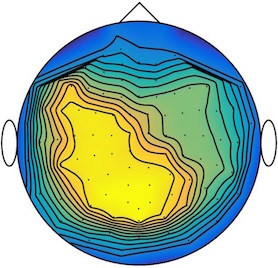

We applied our method to a magnetoencephalography (MEG) dataset. In this setup, brain activity of a subject is recorded (Elekta Neuromag, 306 sensors of which 204 planar gradiometers and 102 magnetometers, sampling frequency 1000Hz) while the subject reacted to the presentation of a target stimulus by pressing either the left or the right button.

Data is preprocessed applying signal space separation correction, interpolation of noisy sensors, and realignment of data into a subject-specific head position (MaxFilter, Elekta Neuromag). The signal was then filtered (low pass 40HZ), and artifacts such as blinks and heartbeats removed thanks to Signal-Space Projection using the Brainstorm software222http://neuroimage.usc.edu/brainstorm. The samples we used for our barycenter computations are an average of the norm of the two gradiometers for each channel from stimulation onto 50ms and the classes were left or right button.

| Class 1 | Class 2 | ||||||

|

|

|

|

|

|

|

|

| Sample 1 | Sample 2 | Sample 3 | Mean | Sample 1 | Sample 2 | Sample 3 | Mean |

|

|

|

|

|

|

|

|

This results in two classes of recordings, one for each pressed button. We aim at computing a representative activity map for each class using Wasserstein barycenters. For each class we have recordings each having samples located on the vertices of an hexahedral mesh of a hemisphere (corresponding to a MEG recording helmet). These recorded values are positive by construction, and we rescale them linearly to impose . Figure 6, top row, shows some samples from this dataset, displayed using interpolated colors as well as iso-level curves. The black dots represent the position of the electrodes on the half-sphere of the helmet, flattened on a 2-D disk.

We computed TV-regularized barycenters independently for each class by solving (16) with the TV regularization using the projected gradient descent method (22). We used a squared Euclidean metric (24) on the flattened hemisphere. Since the data is defined on an irregular graph, instead of (23), we use a graph-based discrete gradient. We denote the graph which connects neighboring electrodes. The gradient operator on the graph is

The total variation on this graph is then obtained by using , the norm, i.e. we use in (23).

Figure 6 compares the naive barycenters (i.e. the usual mean), barycenters obtained without regularization (i.e. ) and barycenters computed with an increasing regularization strength . The input histograms being very noisy, the use of regularization is important to make the area of significant activity emerge from the noise. The use of a TV regularization helps to keep a sharp transition between active and non-active regions.